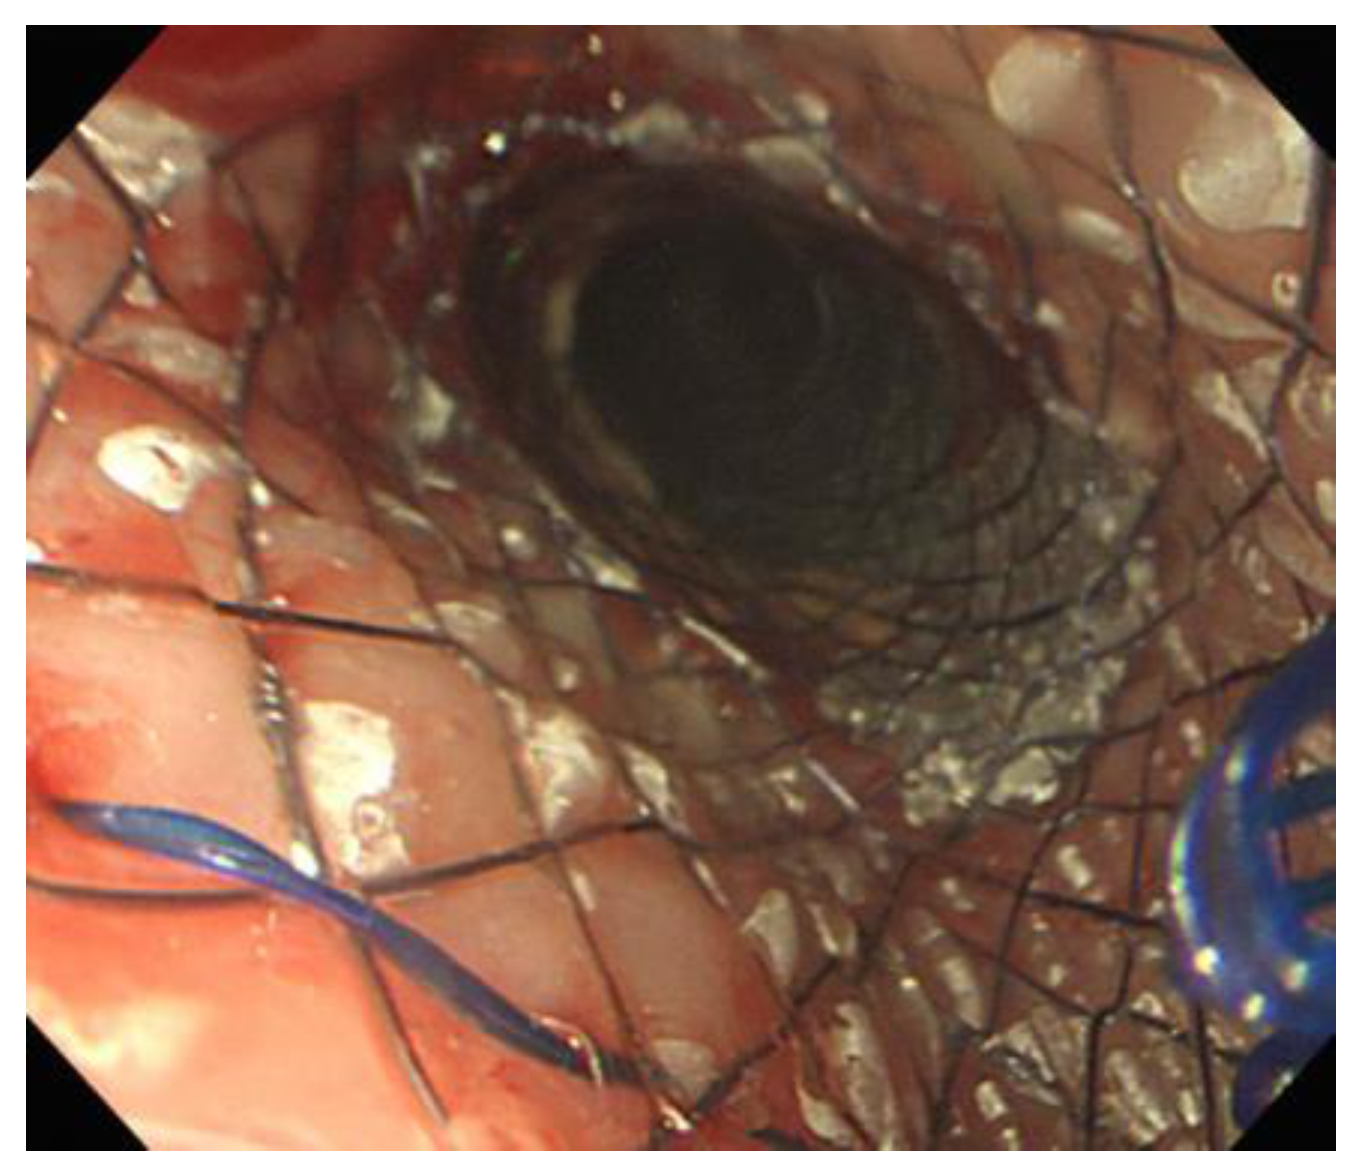

2. Case Report